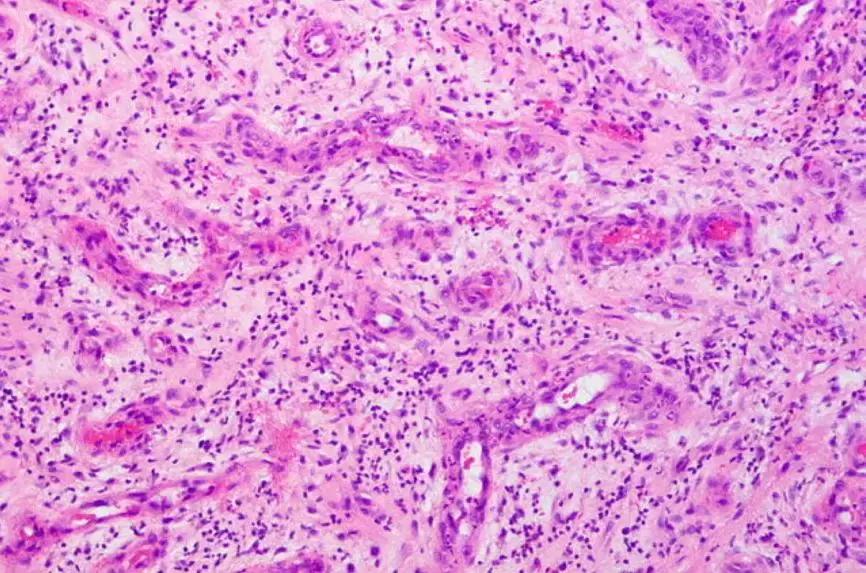

机化(Organization):肉芽组织替代原有结构的过程;肺炎(Pneumonia):炎性反应导致肺泡结构或功能异常。

由增生的成纤维细胞和肌成纤维细胞及其产生的胶原构成,伴有炎性细胞浸润

机化性肺炎(Organizing pneumonia):就是指炎性反应导致肉芽组织填充气腔(包括肺泡管、肺泡囊和肺泡,偶可累及细支气管)的一类肺部疾病。

机化性肺炎的病理学表现:呈小叶中心、斑片性分布特点

⇒ Masson小体

简而言之,机化性肺炎是指肺泡管和肺泡腔内机化(「机化性肺炎」),伴或不伴细支气管内机化(「息肉样闭塞性细支气管炎」)。